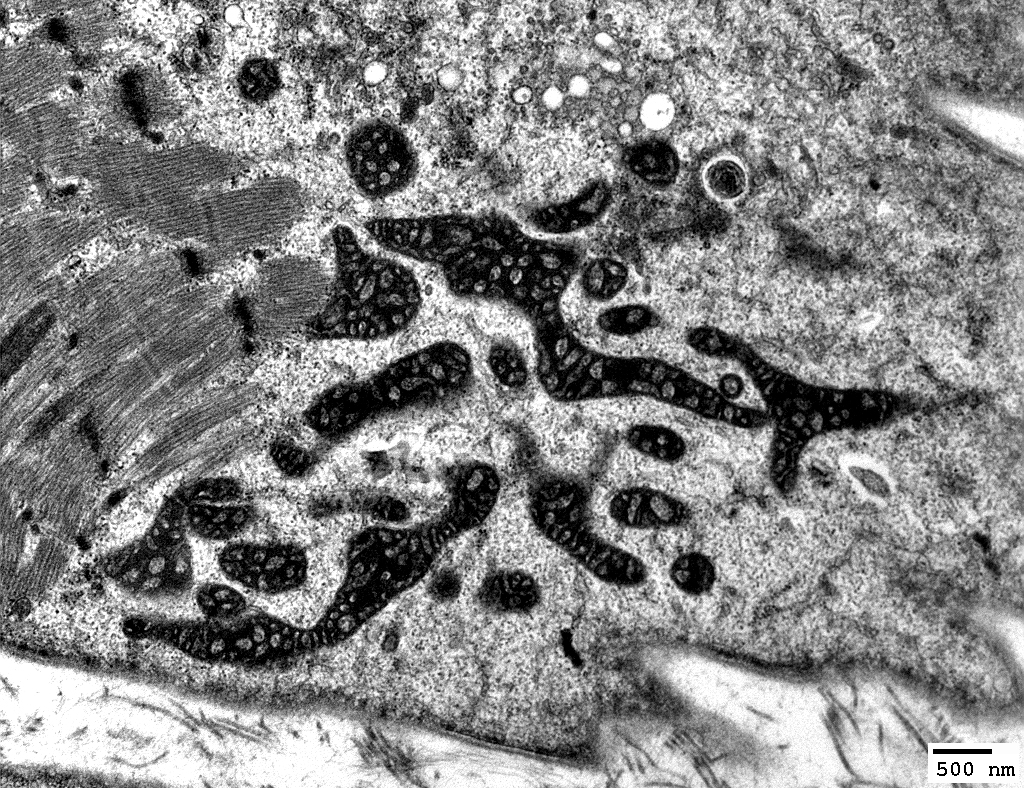

Twinkle: Muscle Ultrastructure

Mitochondrial Proliferation

Mitochondria: Subsarcolemmal accumulations

Many mitochondria are abnormal: Large; Long; Dark-stained

From: R Schmidt; C Cai

Many mitochondria in 1 fiber are: Large; Dark-stained

From: R Schmidt